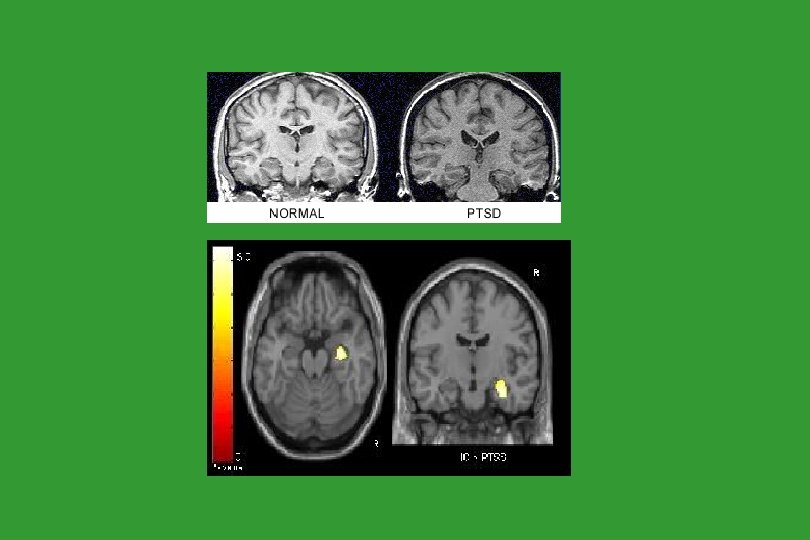

Lateral Ventricles Measures in an 11 Year Old Maltreated Male with Chronic PTSD, Compared with a Healthy, Non-Maltreated Matched Control (De Bellis et al. , 1999)

Rauch Brain scans